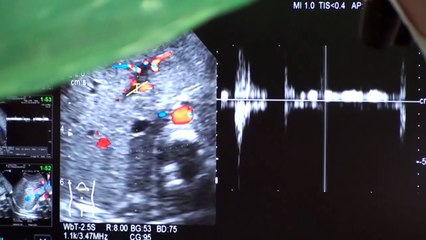

El Dr. Pepe Bandera responde tus dudas acerca de la resequedad en la garganta y las células madre. No te pierdas todos los días Sale el Sol a las 9 a.m. por ...